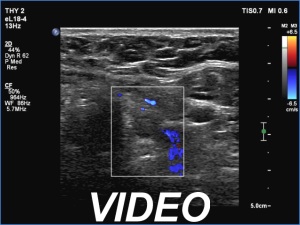

Clinical presentation: A 19-yr-old, overweighted woman (161 cm height, 91 kg weight) was referred for aspiration cytology of a nodule. Neck and thyroid ultrasound were performed because of repeated upper airway infections.

Ultrasonography. The thyroid was echonormal. Using higher frequency three discrete hypoechoic lesions were found, one in the middle dorsal part of the right lobe, one in the middle and a third one in the lower dorsal part of the left lobe. By decreasing the frequency, the presence of only the third one could be confirmed.

Comment. It is a rule that larger the distance from the probe worse the permeability of ultrasound wave. This can lead in certain patients (overweighted ones or frequently in men) that the dorsal part of the thyroid lobe can deceptively look darker, i.e. hypoechoic. If we have any doubt, by lowering the frequency i.e. increasing the penetrance, the real situation can be much better to judge.

This happened in this patient. If we would trust the pattern gained by higher frequency settings, we would falsely diagnose at least one additional nodule.